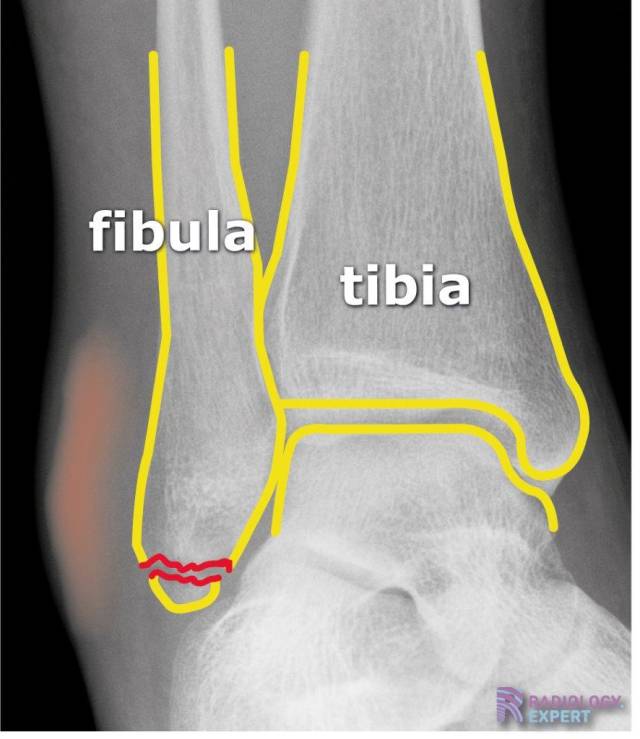

Weber A fractuur Weber A fractuur

Klik op afbeelding om overlay te zien